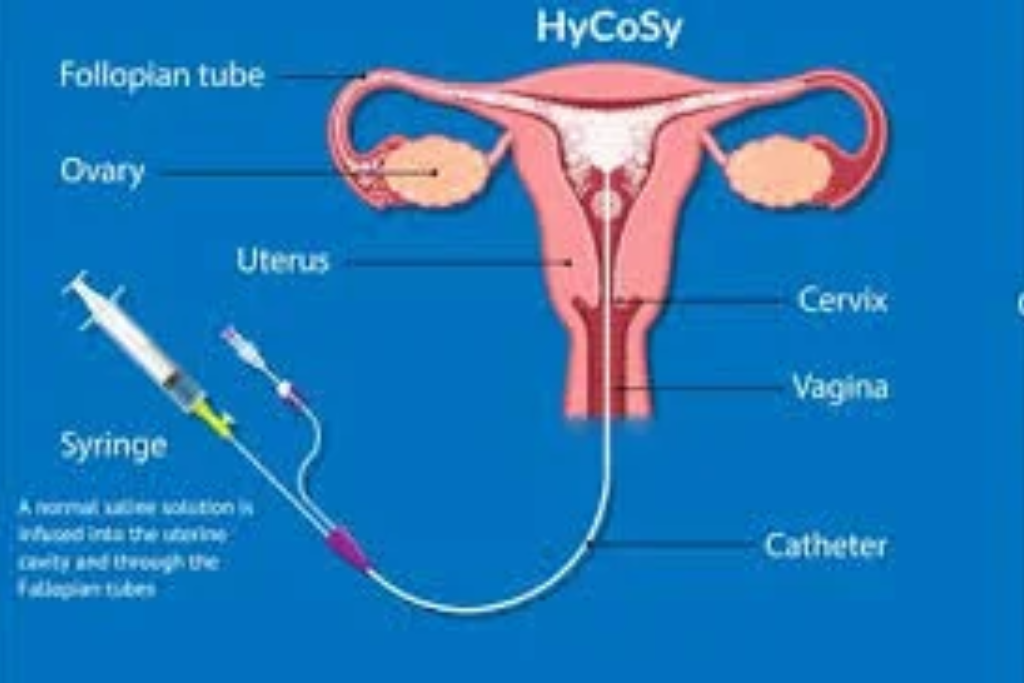

HyCoSy (Hysterosalpingo-Contrast Sonography)

An ultrasound technique using contrast fluid to check if fallopian tubes are open.

Why are HyCoSy and SIS tests recommended?

These tests help in identifying fallopian tube blockages and uterine abnormalities, which are common causes of infertility, allowing better treatment planning.